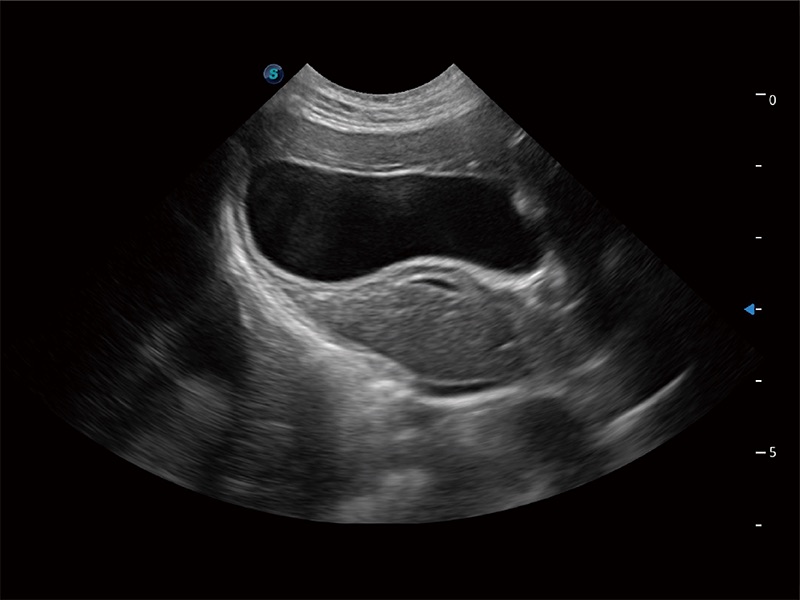

(犬)肝脏

(猫)胆囊

(犬)胎儿主动脉弓立体血流

(犬)四腔心MQA

(犬)肠道

(犬)肾脏显微血流

(犬)胎儿四腔心

(猫)二尖瓣M型

(犬)二腔心血流

优异的基础图像

ProPet 80 全新的动物超声智能软件和丰富的探头群,为动物医生提供了高清晰度和精细分辨率的图像,无论在宠物、马科、畜牧还是实验室动物等应用中都可以轻松应对,为您的日常工作带来满意的体验。